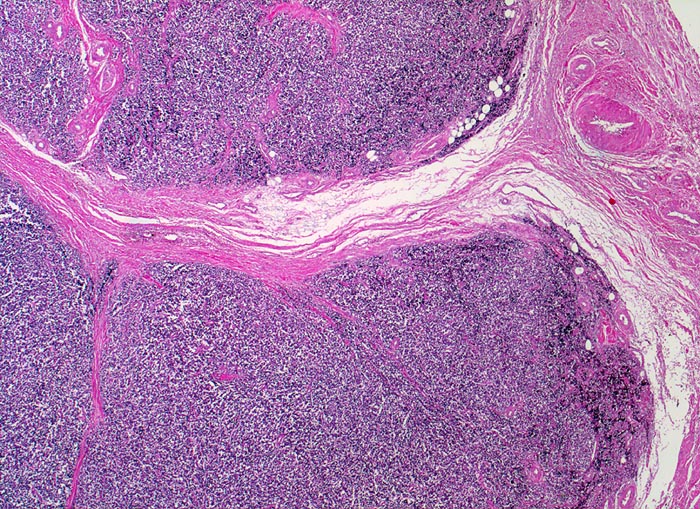

• Durch Bindegewebssepten abgegrenzte Knoten (lobuläre Architektur).

• Blauer, klein- und rundzelliger Tumor.

• Uniforme Zellen mit schmalem, kaum abgrenzbarem Zytoplasmasaum und unscharfen Zellgrenzen. Rundliche oder ovale Zellkerne mit leicht vergröbertem Chromatin und punktförmigen kleinen Nukleolen.

Die Tumoren sind makroskopisch grauweiss und wachsen destruktiv und infiltrativ. Nekrosen und Einblutungen sind häufig. Histologisch lassen sich solide Rasen monomorpher, kleiner, rundlicher Tumorzellen mit dichtem Chromatin und wenig Zytoplasma nachweisen (sog. small-blue-round cells). Metastasen treten vor allem in der Lunge und in anderen Skelettabschnitten auf. Die Differentialdiagnose klein-blau- und rundzelliger Tumoren im Kindesalter ist breit. Kleinzellige Osteosarkome, Neuroblastome, Lymphome und mesenchymale Chondrosarkome können ein histologisch ähnliches Bild zeigen, speziell in kleinen Biopsien, und müssen mit Hilfe von (molekularen) Zusatzuntersuchungen und unter Einbezug klinischer und radiologischer Befunde voneinander abgegrenzt werden.